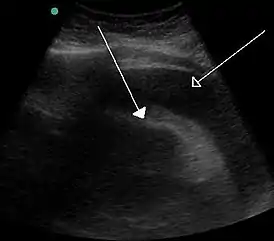

![]() Скопление большого количества жидкости между листками перикарда, видимое при ультразвуковом исследовании. | |

Данное состояние угрожает жизни и без своевременного адекватного лечения может привести к смерти больного. Больной отмечает у себя наличие характерных для сердечной недостаточности жалоб. При разрыве миокарда наблюдается триада Бека, которая включает в себя гипотензию, набухание вен шеи и глухие сердечные тоны. Аускультативно обнаруживаются приглушенные тоны сердца, при ультразвуковом исследовании обнаруживается жидкость между листками перикарда.